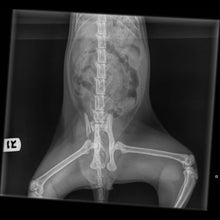

Every week we're contacted by vets or directly by owners because an animal has been injured or is unwell and they're unable to afford their care or surgery. Many owners feel that they are left with no choice but to euthanise.

Thats where HUHA steps in! We do our best to ensure the animal gets the care or surgery they desperately need.